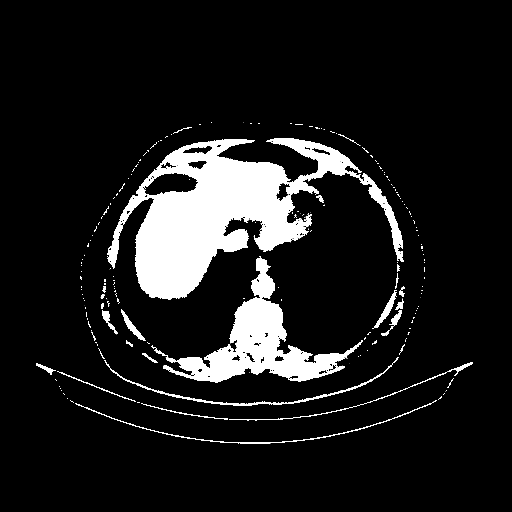

Generated VENOUS CT scan (A→B translation)

Full window (WL 1023.5, WW 4095 β†’ Low βˆ’1024, High +3071)

Actual HU range: [-1024.0, 3071.0]